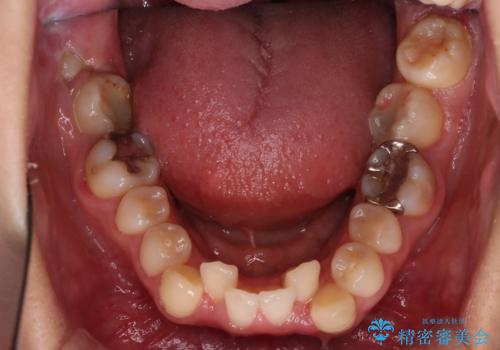

【抜歯矯正】犬歯抜歯による矯正。八重歯を治したい

- 八重歯を主訴に来院された患者様です。

抜歯矯正において、通常では4番(第一小臼歯)が抜歯の対象となることが多いのですが、今回は3番(犬歯)の歯肉退縮や装置の特性を考慮した治療計画となります。

下顎に関しては、半年ほどワイヤー矯正にてリカバリーを行なっております。